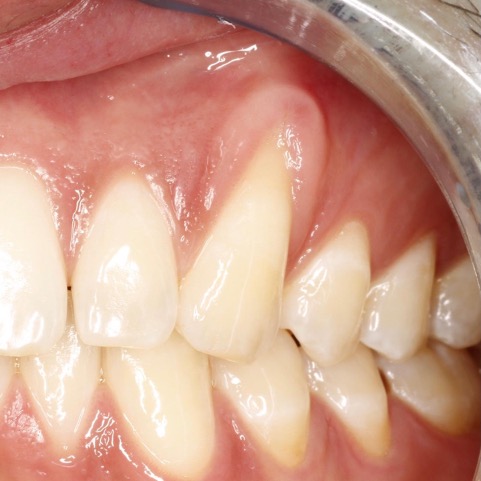

TERAPIA DELLE RECESSIONI GENGIVALI

La terapia delle recessioni gengivali consiste nel ricostituire i tessuti gengivali perduti per ricoprire le radici esposte dei denti e restituire un’adeguata estetica al sorriso.

La procedura prevede un prelievo di tessuto connettivo dal palato, il trattamento della radice esposta, la preparazione dell’innesto e la sua collocazione nel sito ricevente.